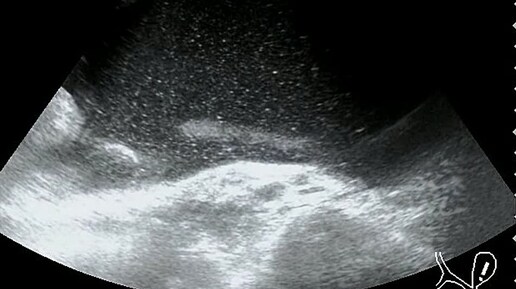

Видео к статье: "Свободная жидкость в брюшной полости"https://dzen.ru/a/Z-1KdOK-KyrjRiGF

Ультразвуковые находки от врача УЗД Зорина Я.П.